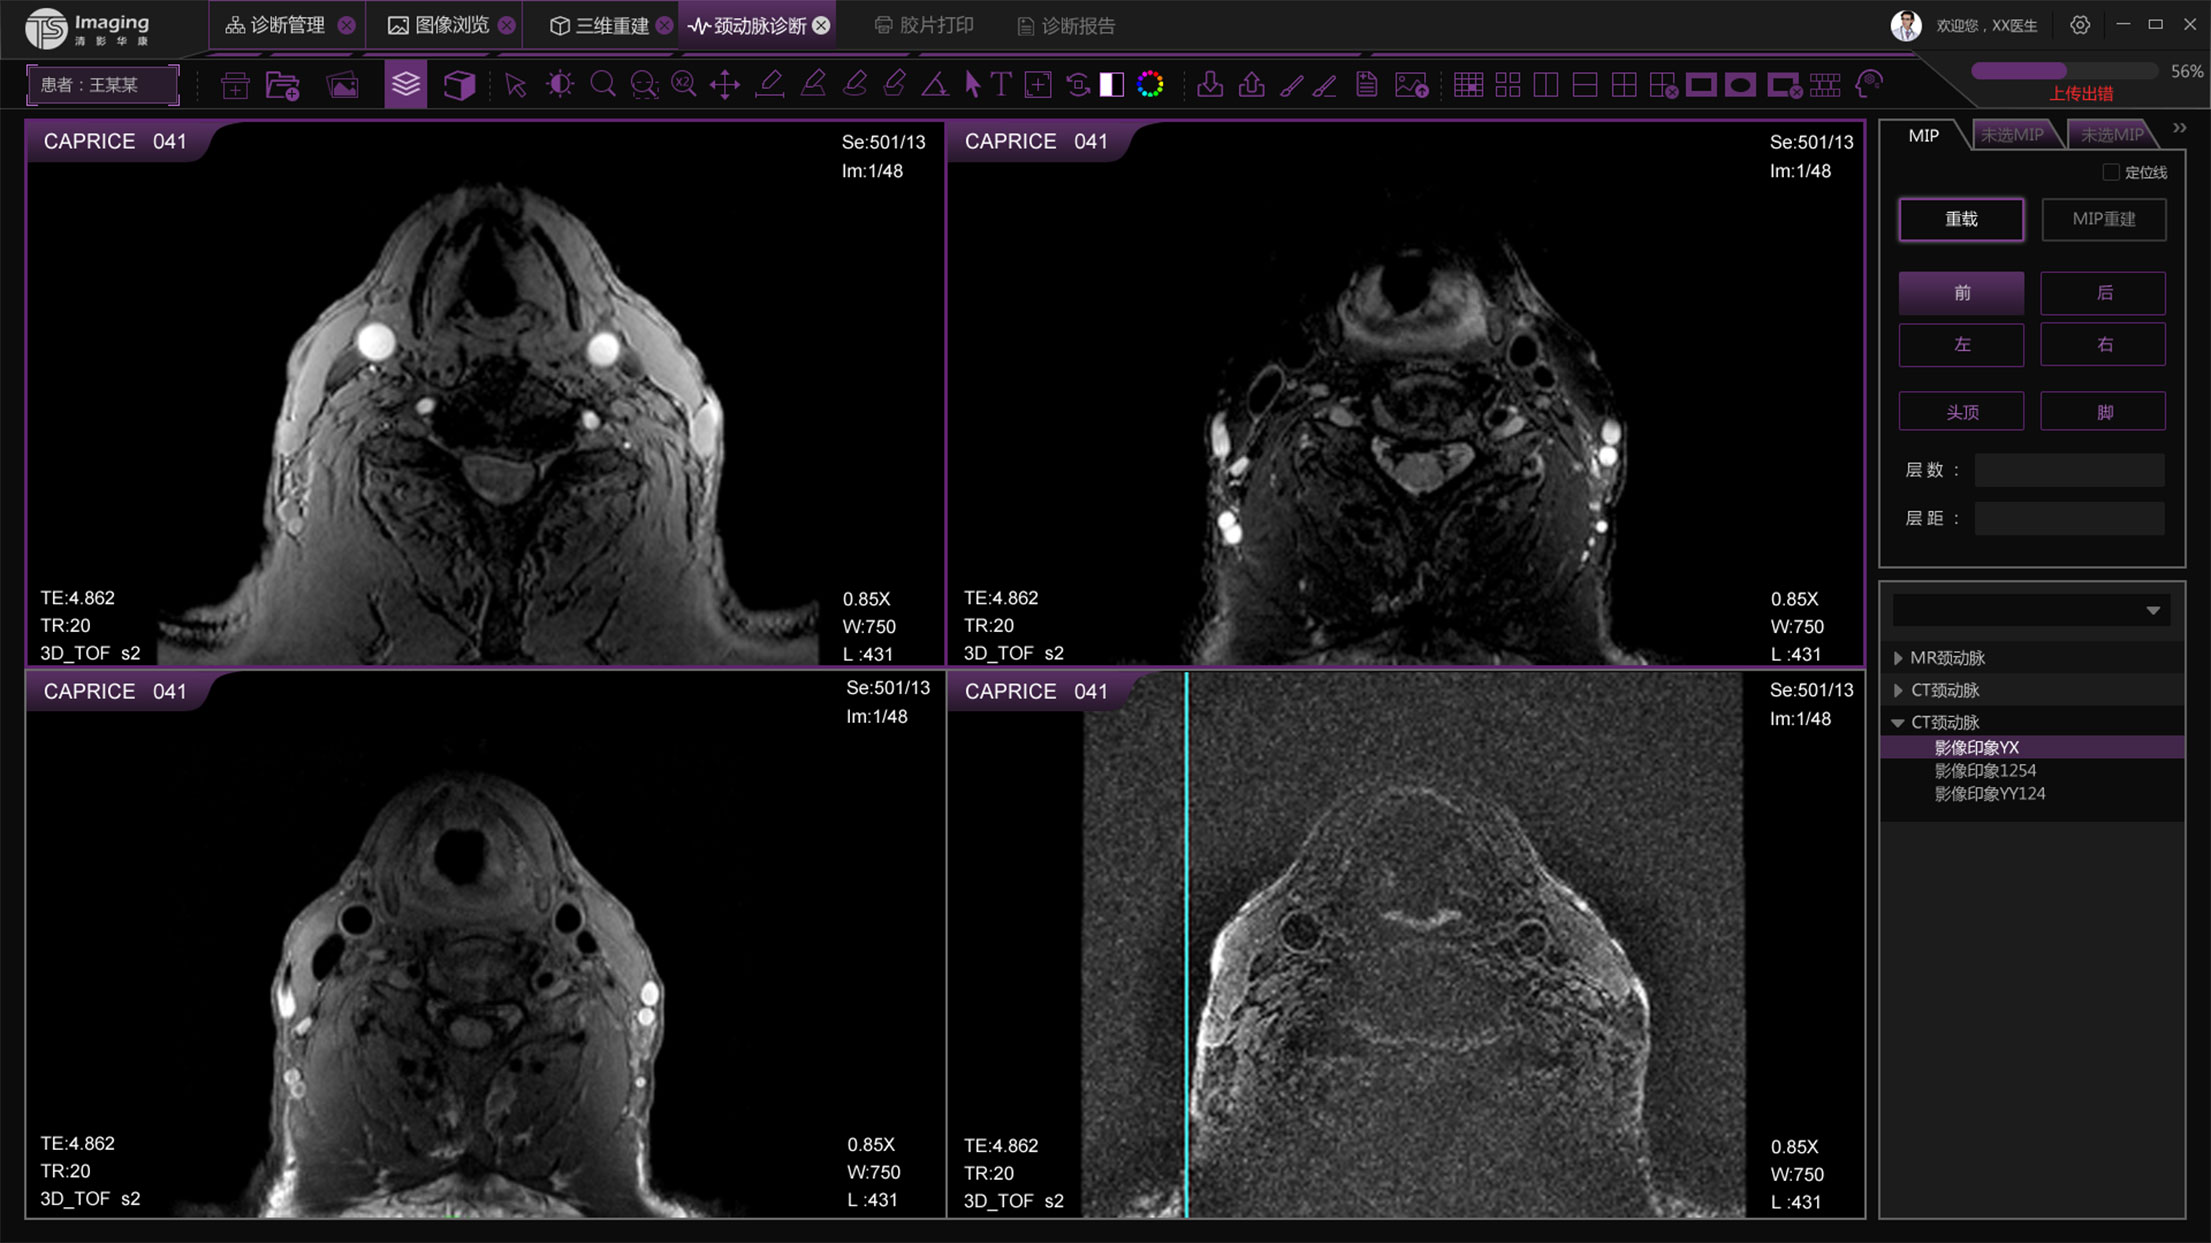

頸動(dòng)脈診斷頁面

頸動(dòng)脈診斷頁面整體布局和三維重建比較相似,最大的區(qū)別是右側(cè)的操作區(qū)域,血管分析都為按鍵操作,通過間隔的大小分成三部分。單層切片除了按鍵還有下拉菜單的操作。

頸動(dòng)脈診斷原型